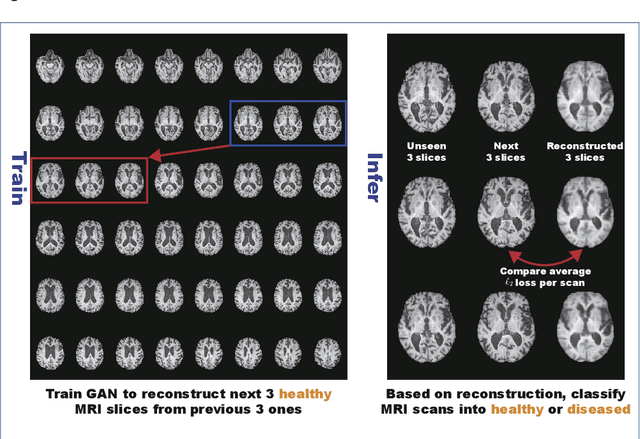

Abstract:Unsupervised learning can discover various unseen diseases, relying on large-scale unannotated medical images of healthy subjects. Towards this, unsupervised methods reconstruct a 2D/3D single medical image to detect outliers either in the learned feature space or from high reconstruction loss. However, without considering continuity between multiple adjacent slices, they cannot directly discriminate diseases composed of the accumulation of subtle anatomical anomalies, such as Alzheimer's Disease (AD). Moreover, no study has shown how unsupervised anomaly detection is associated with either disease stages, various (i.e., more than two types of) diseases, or multi-sequence Magnetic Resonance Imaging (MRI) scans. Therefore, we propose unsupervised Medical Anomaly Detection Generative Adversarial Network (MADGAN), a novel two-step method using GAN-based multiple adjacent brain MRI slice reconstruction to detect various diseases at different stages on multi-sequence structural MRI: (Reconstruction) Wasserstein loss with Gradient Penalty + 100 L1 loss-trained on 3 healthy brain axial MRI slices to reconstruct the next 3 ones-reconstructs unseen healthy/abnormal scans; (Diagnosis) Average L2 loss per scan discriminates them, comparing the ground truth/reconstructed slices. For training, we use 1,133 healthy T1-weighted (T1) and 135 healthy contrast-enhanced T1 (T1c) brain MRI scans. Our Self-Attention MADGAN can detect AD on T1 scans at a very early stage, Mild Cognitive Impairment (MCI), with Area Under the Curve (AUC) 0.727, and AD at a late stage with AUC 0.894, while detecting brain metastases on T1c scans with AUC 0.921.

Abstract:Unsupervised learning can discover various unseen diseases, relying on large-scale unannotated medical images of healthy subjects. Towards this, unsupervised methods reconstruct a single medical image to detect outliers either in the learned feature space or from high reconstruction loss. However, without considering continuity between multiple adjacent images, they cannot directly discriminate diseases composed of the accumulation of subtle anatomical anomalies, such as Alzheimer's Disease (AD). Moreover, no study shows how unsupervised anomaly detection is associated with disease stages. Therefore, we propose a two-step method using Generative Adversarial Network-based multiple adjacent brain MRI slice reconstruction to detect AD at various stages: (Reconstruction) Wasserstein loss with Gradient Penalty + L1 loss---trained on 3 healthy slices to reconstruct the next 3 ones---reconstructs unseen healthy/AD cases; (Diagnosis) Average/Maximum loss (e.g., L2 loss) per scan discriminates them, comparing the reconstructed/ground truth images. The results show that we can reliably detect AD at a very early stage with Area Under the Curve (AUC) 0.780 while also detecting AD at a late stage much more accurately with AUC 0.917; since our method is unsupervised, it should also discover and alert any anomalies including rare disease.